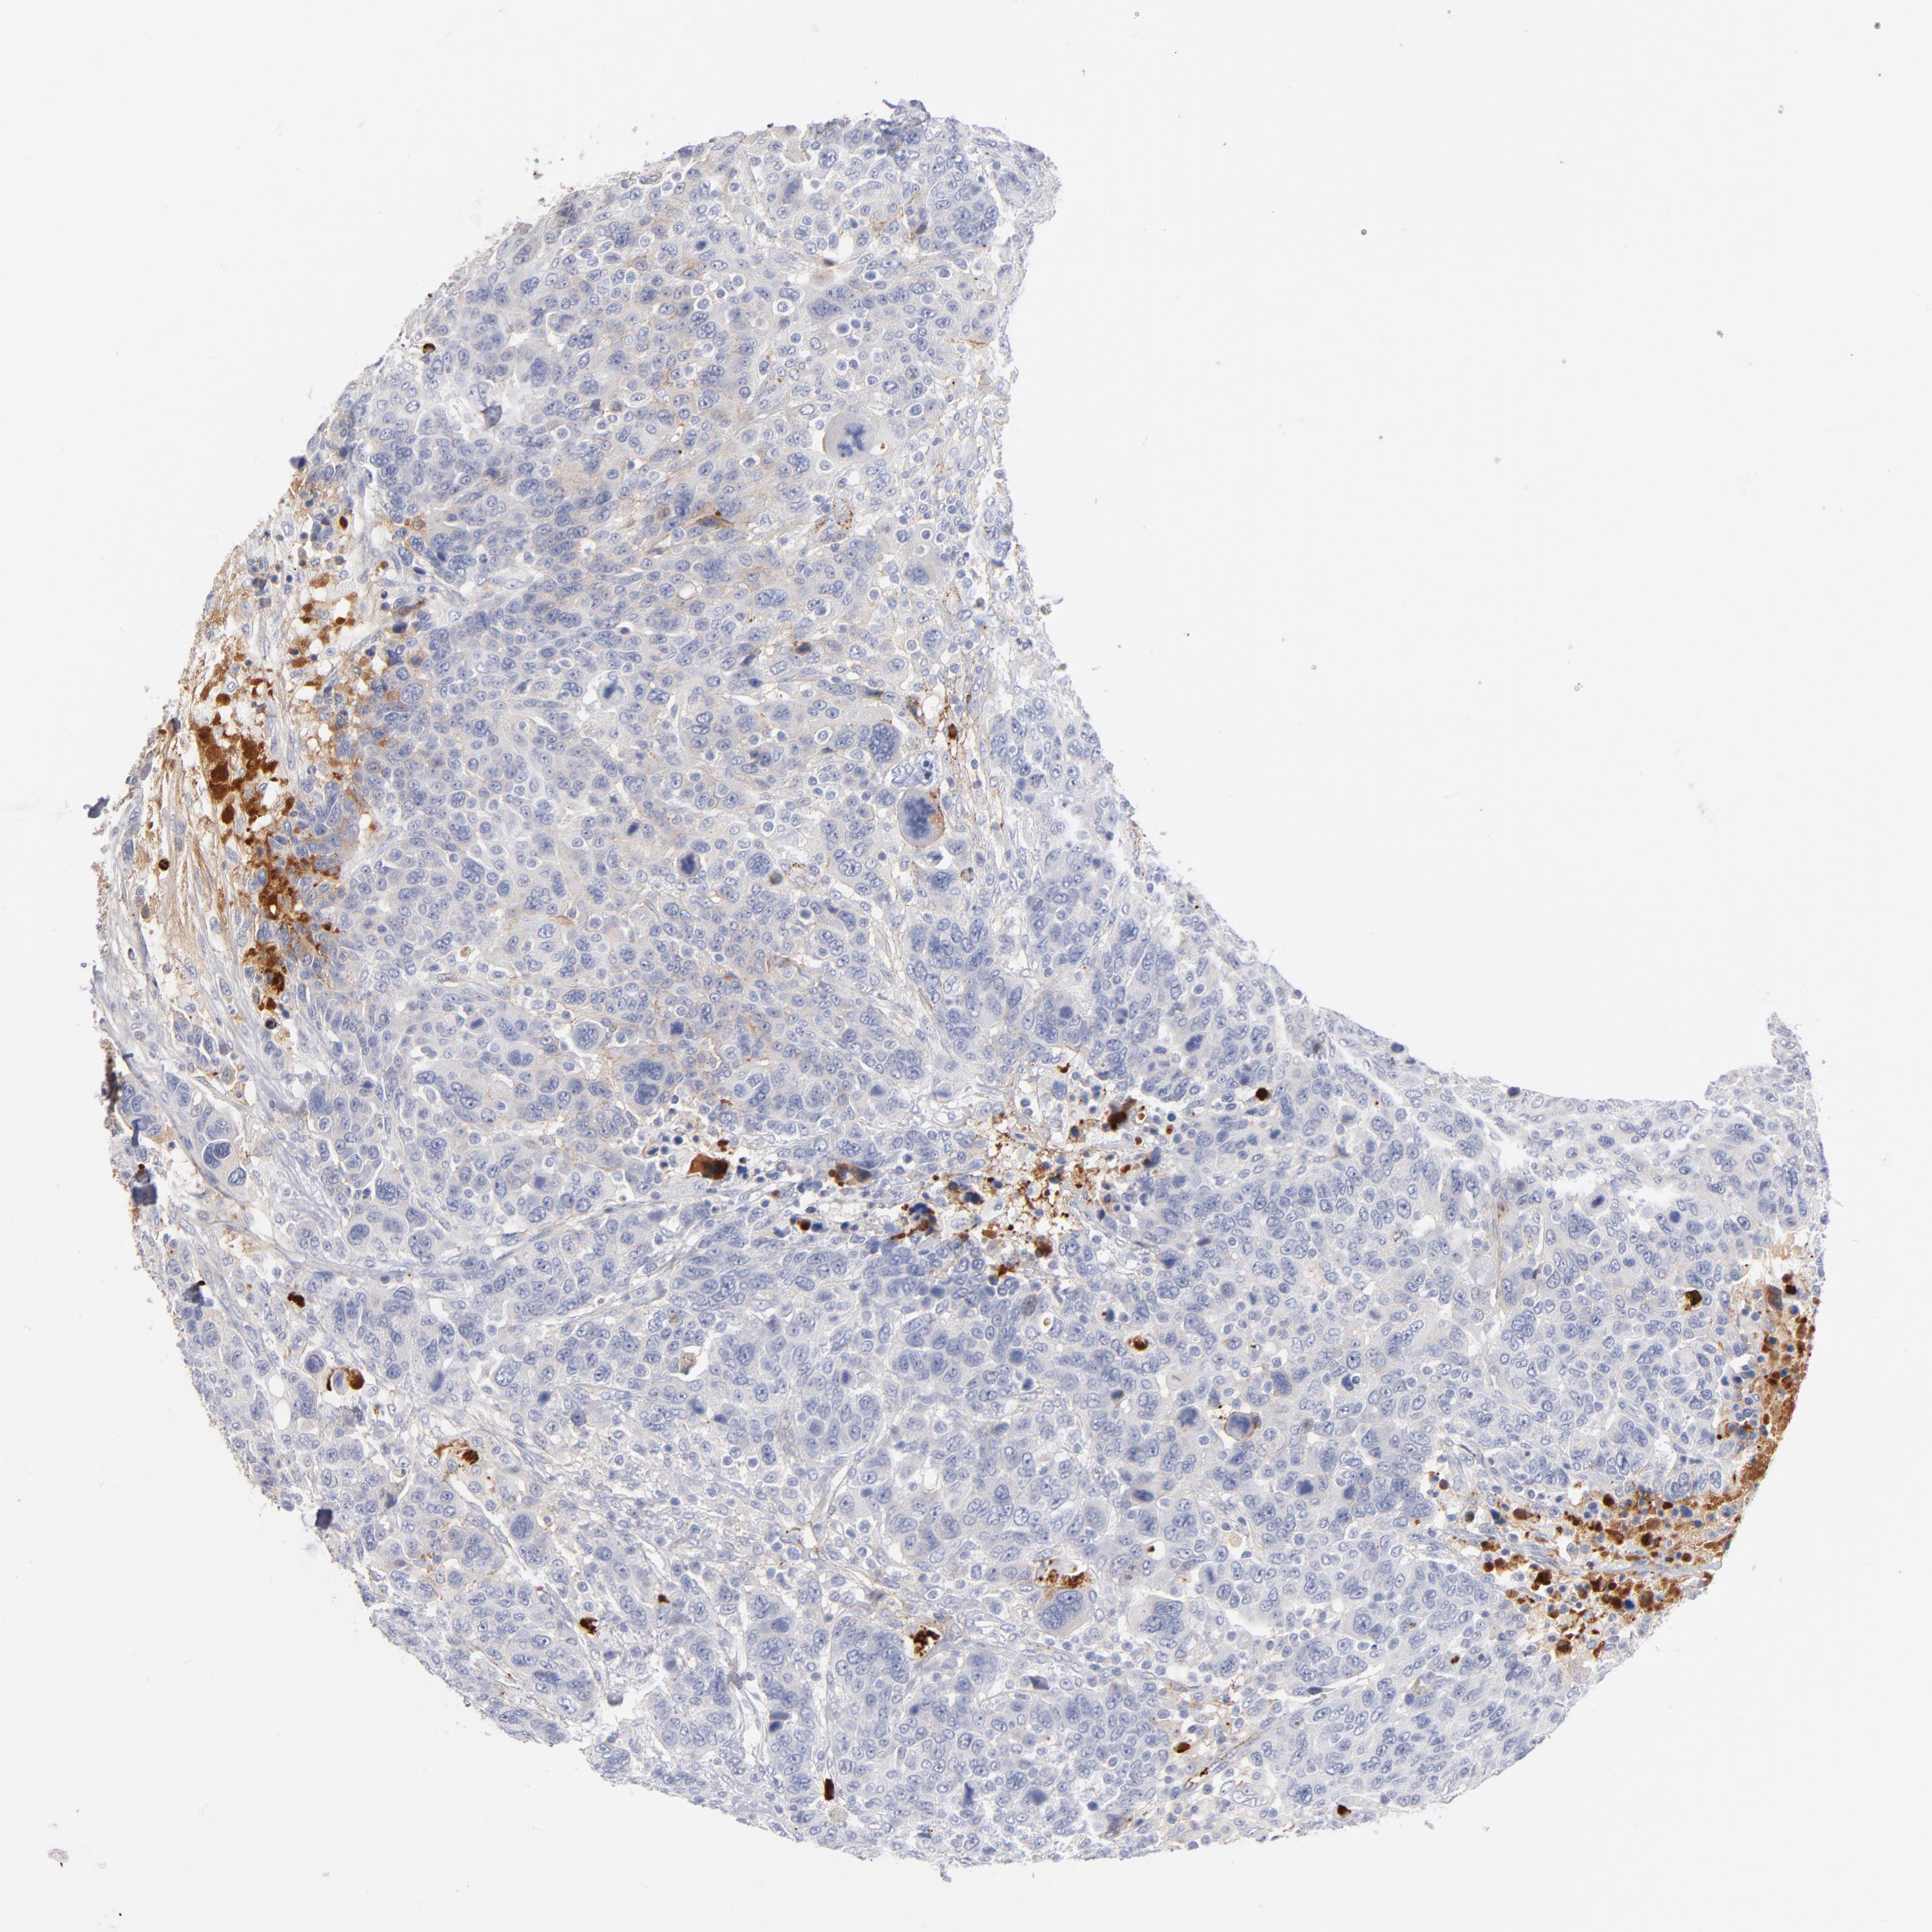

CANCER BREAST CANCER Show tissue menu

BRCA TCGA BRCA VALIDATION PROTEIN EXPRESSION